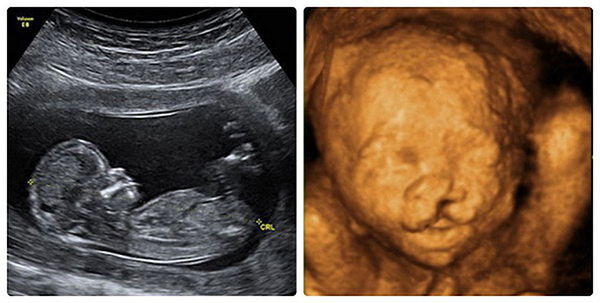

Siêu âm thai nhi là một phương pháp chẩn đoán y khoa phổ biến bằng hình ảnh giúp theo dõi sự phát triển cũng như phát hiện những dị tật thai nhi bẩm sinh.

Siêu âm thai nhi là phương pháp không xâm lấn, sử dụng sóng âm để chẩn đoán hình ảnh thai nhi và một số cơ quan khác như: Nhau thai, tử cung sản phụ trong quá trình mang thai. Nhờ siêu âm thai nhi bác sĩ sẽ nắm bắt được sự phát triển cũng như tình trạng sức khỏe của em bé.

Bản chất của quá trình siêu âm thai nhi là sóng âm từ máy siêu âm được truyền tử cung người mẹ, các tín hiệu sóng từ việc phản xạ lại của cơ thể bé cũng như các cơ quan của mẹ sẽ được máy tính dịch thành các hình ảnh. Do đó khi siêu âm thai nhi chúng ta có thể nhìn thấy hình dáng, cử động và vị trí của em bé.

Hiện nay các loại siêu âm rất đa dạng: Siêu âm 2D, 3D, 4D hoặc siêu âm Doppler màu. Do vậy, mẹ bầu có thể lựa chọn tùy ý khi muốn tiến hành siêu âm thai nhi.